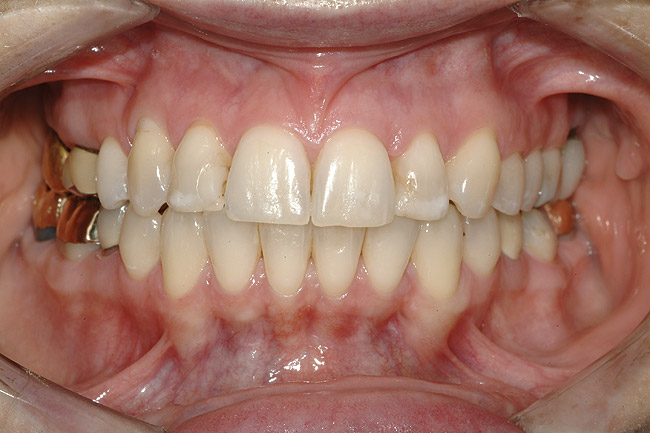

FUNCŢIONAL: La majoritatea dinţilor posteriori ai pacientei ce erau restauraţi cu coroane (fig. 6, 7) era importantă interpretarea minuţioasă a istoricului pacientei şi a rezultatelor evaluării ocluzale. Coroanele din aur de la nivelul 1.7. şi 1.4. prezentau orificii de uzură pe suprafeţele ocluzale, cu semne de minimă uzură pe celelalte coroane posterioare şi la dentiţia naturală. Era evidentă o uzură moderată pe coroana din aur a molarului 4.7.

Traumatismul ocluzal primar s-a observat la dinţii 1.5. şi 2.5. În intercuspidare maximă, s-a notat ocluzie deschisă la segmentele dentare frontale 1.3.-2.3. şi 3.3.-4.3. Dinţii 1.6. şi 4.6., precum şi 2.6. şi 3.6. erau în angrenaj invers (fig. 5, 8). Pacienta prezenta o ocluzie Angle Clasa I. Având în vedere rezultatele istoricului şi examinării s-a stabilit un diagnostic de disfuncţie ocluzală.

DENTO-FACIAL: Evaluarea zâmbetului pacientei a evidenţiat o dinamică labială maxilară medie şi afişarea ţesuturilor la zâmbire (fig. 2). Nivelurile gingivale maxilare inegale, exostoza osoasă vestibulară vizibilă corespunzător 1.6., dinţii rotaţi sau malpoziţionaţi, coloraţia de pe mai mulţi dinţi frontali, o „linie a surâsului inversată” , asimetria dentară şi un plan ocluzal maxilar neregulat reprezentau puncte semnificative în cadrul evaluării dentofaciale. Dorinţa pacientei de a avea un zâmbet ideal sau „generat de media” a accentuat dificultatea cazului. Dinamica labială maxilară medie şi afişarea în consecinţă a ţesuturilor a dictat evaluarea riscului pentru acest caz.